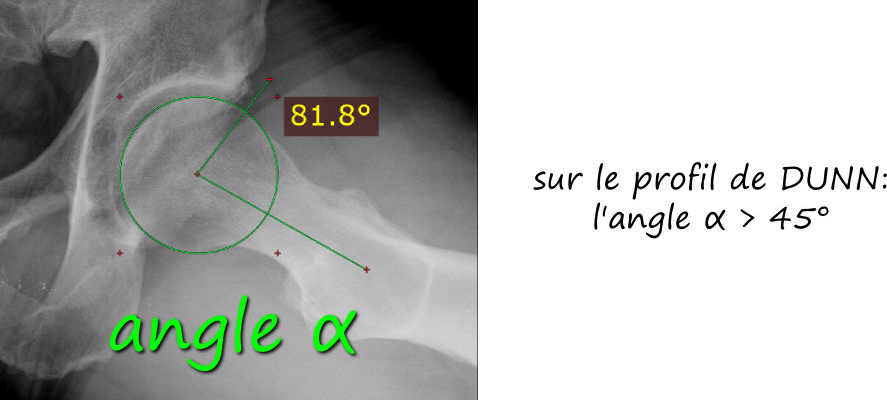

- par effet came: le facteur prédominant est l’excroissance osseuse de la face antérieure du col fémoral

Le conflit fémoro acétabulaire se décèle sur de simples radiographies de la hanche, notemment sur le profil de DUNN qui expose la face antérieure du col fémoral. Sur cette radio est estimée l’angle alpha, correpondant à l’angle formé par l’axe du col fémoral et une droite passsant par le centre de la tete fémorale et le point de décrochage de la jonction tete-col, et qui est normalement de l’ordre de 45°; il est augmenté dans les conflits par effet came, comme sur cette radio ci dessous.